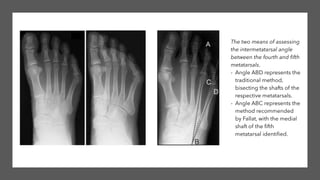

Imaging

Plain Film Radiograph:

1. 4-5 Intermetatarsal Angle > 9 degrees

(Normal is 6.47 degrees per Fallat and

Buckholtz)

2. Lateral Deviation Angle > 8 degrees

(Normal is 2.64 degrees per Fallat and

3. Splay Foot Deformity

4. Plantarflexed 5th metatarsal position

5. Structural changes to 5th metatarsal

head

Imaging Plain Film Radiograph: 1.4-5 Intermetatarsal Angle > 9 degrees (Normal is 6.47 degrees per Fallat and Buckholtz) 2. Lateral Deviation Angle > 8 degrees (Normal is 2.64 degrees per Fallat and Buckholtz) 3. Splay Foot Deformity 4. Plantarflexed 5th metatarsal position 5. Structural changes to 5th metatarsal head